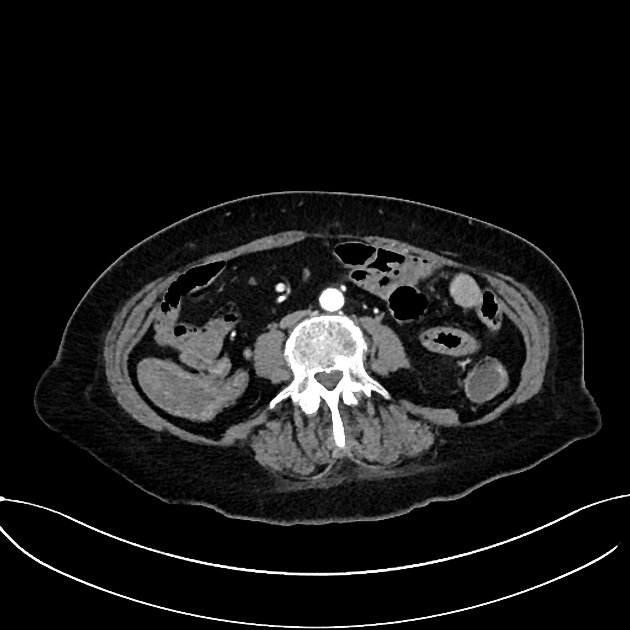

CT Bleeding Study

4 views

Jan 20, 2025

A patient presents with acute hypotension and hematochezia. An estimated 2L of blood loss was recorded in the ED. The patient was referred to general surgery. The bleeding stopped, and the patient remained hemodynamically stable. A colonoscopy was arranged. CT findings suggest an unusual cause of lower gastrointestinal bleeding. Based on the provided CT scan and case history, what is the most likely diagnosis?

Correct answer is Appendiceal hemorrhage due to angiodysplasia